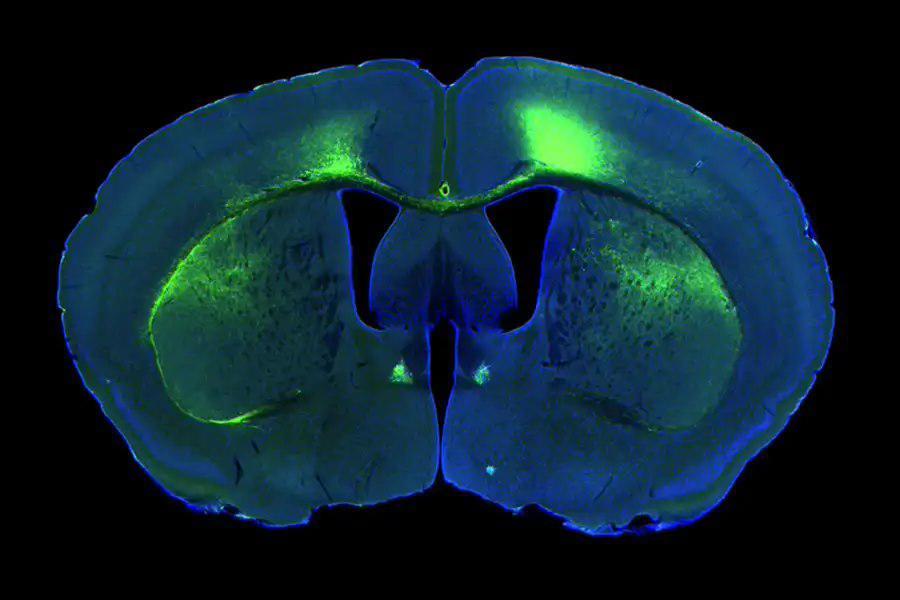

在这项实验中,研究人员在数只小鼠的大脑中植入了探针,并记录了它们在开放环境中移动时的神经元放电模式,同时拍摄了视频记录它们的位置和头部方向。